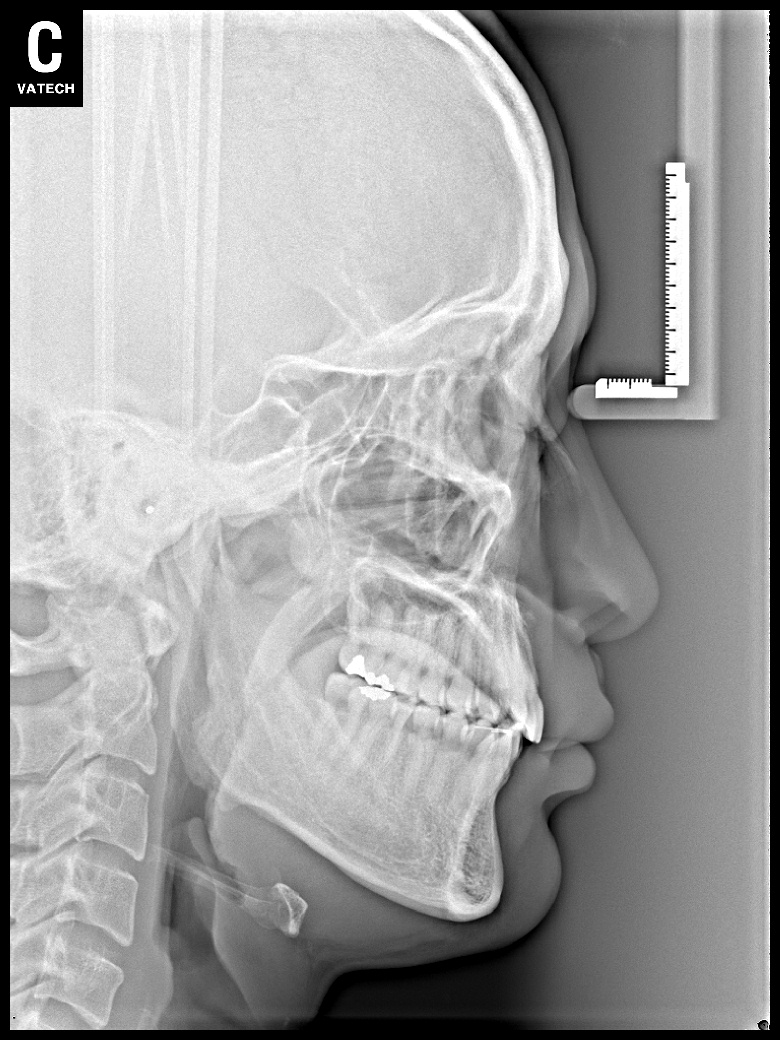

치료 후 사진입니다.